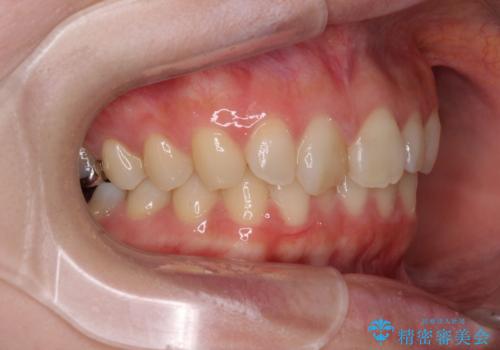

- 近々転勤の予定があるが、早めにインビザラインによる矯正治療を始めたいとのことで来院された患者様です。

上下ともにデコボコの程度は著しいものではなく、インビザラインで十分に対応可能な歯列不正でした。

後戻りによりスペースができてしまうことを避ける目的で、IPR(歯と歯の間を削る)を極力用いない矯正治療を行うこととしました。